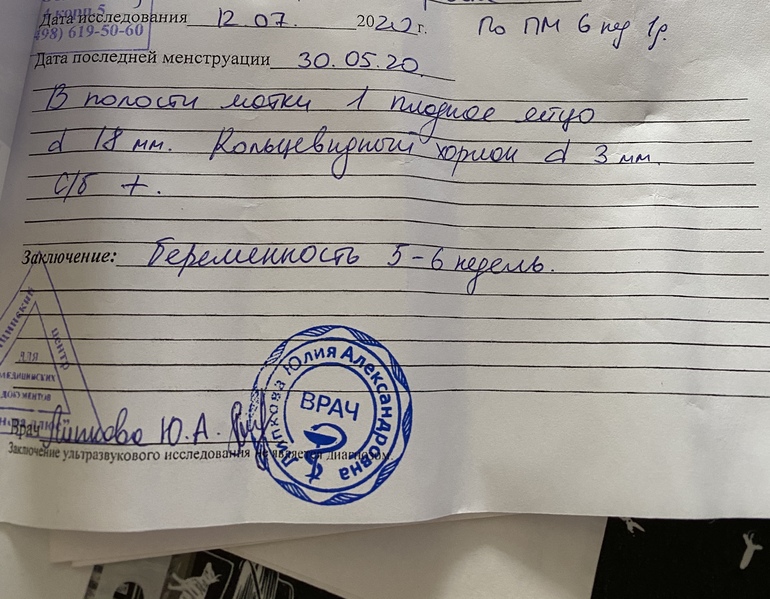

Узи 🥰

Сходила на узи)Пока успокоилась)

Чувствую себя по разному,по утрам всё бесит и тошнит..отвернуло от яиц и помидор и рыбы не ем их.Хочется фруктов,поспать и поплакать)Описание какое то короткое..не написала ктр(но врач сказала что всё хорошо и это главное!Показывала как бьётся сердечко на мониторе незабываемое чувство 🥰

Ну вот узистка какая то молодая была ни ктр не написала ни чсс...